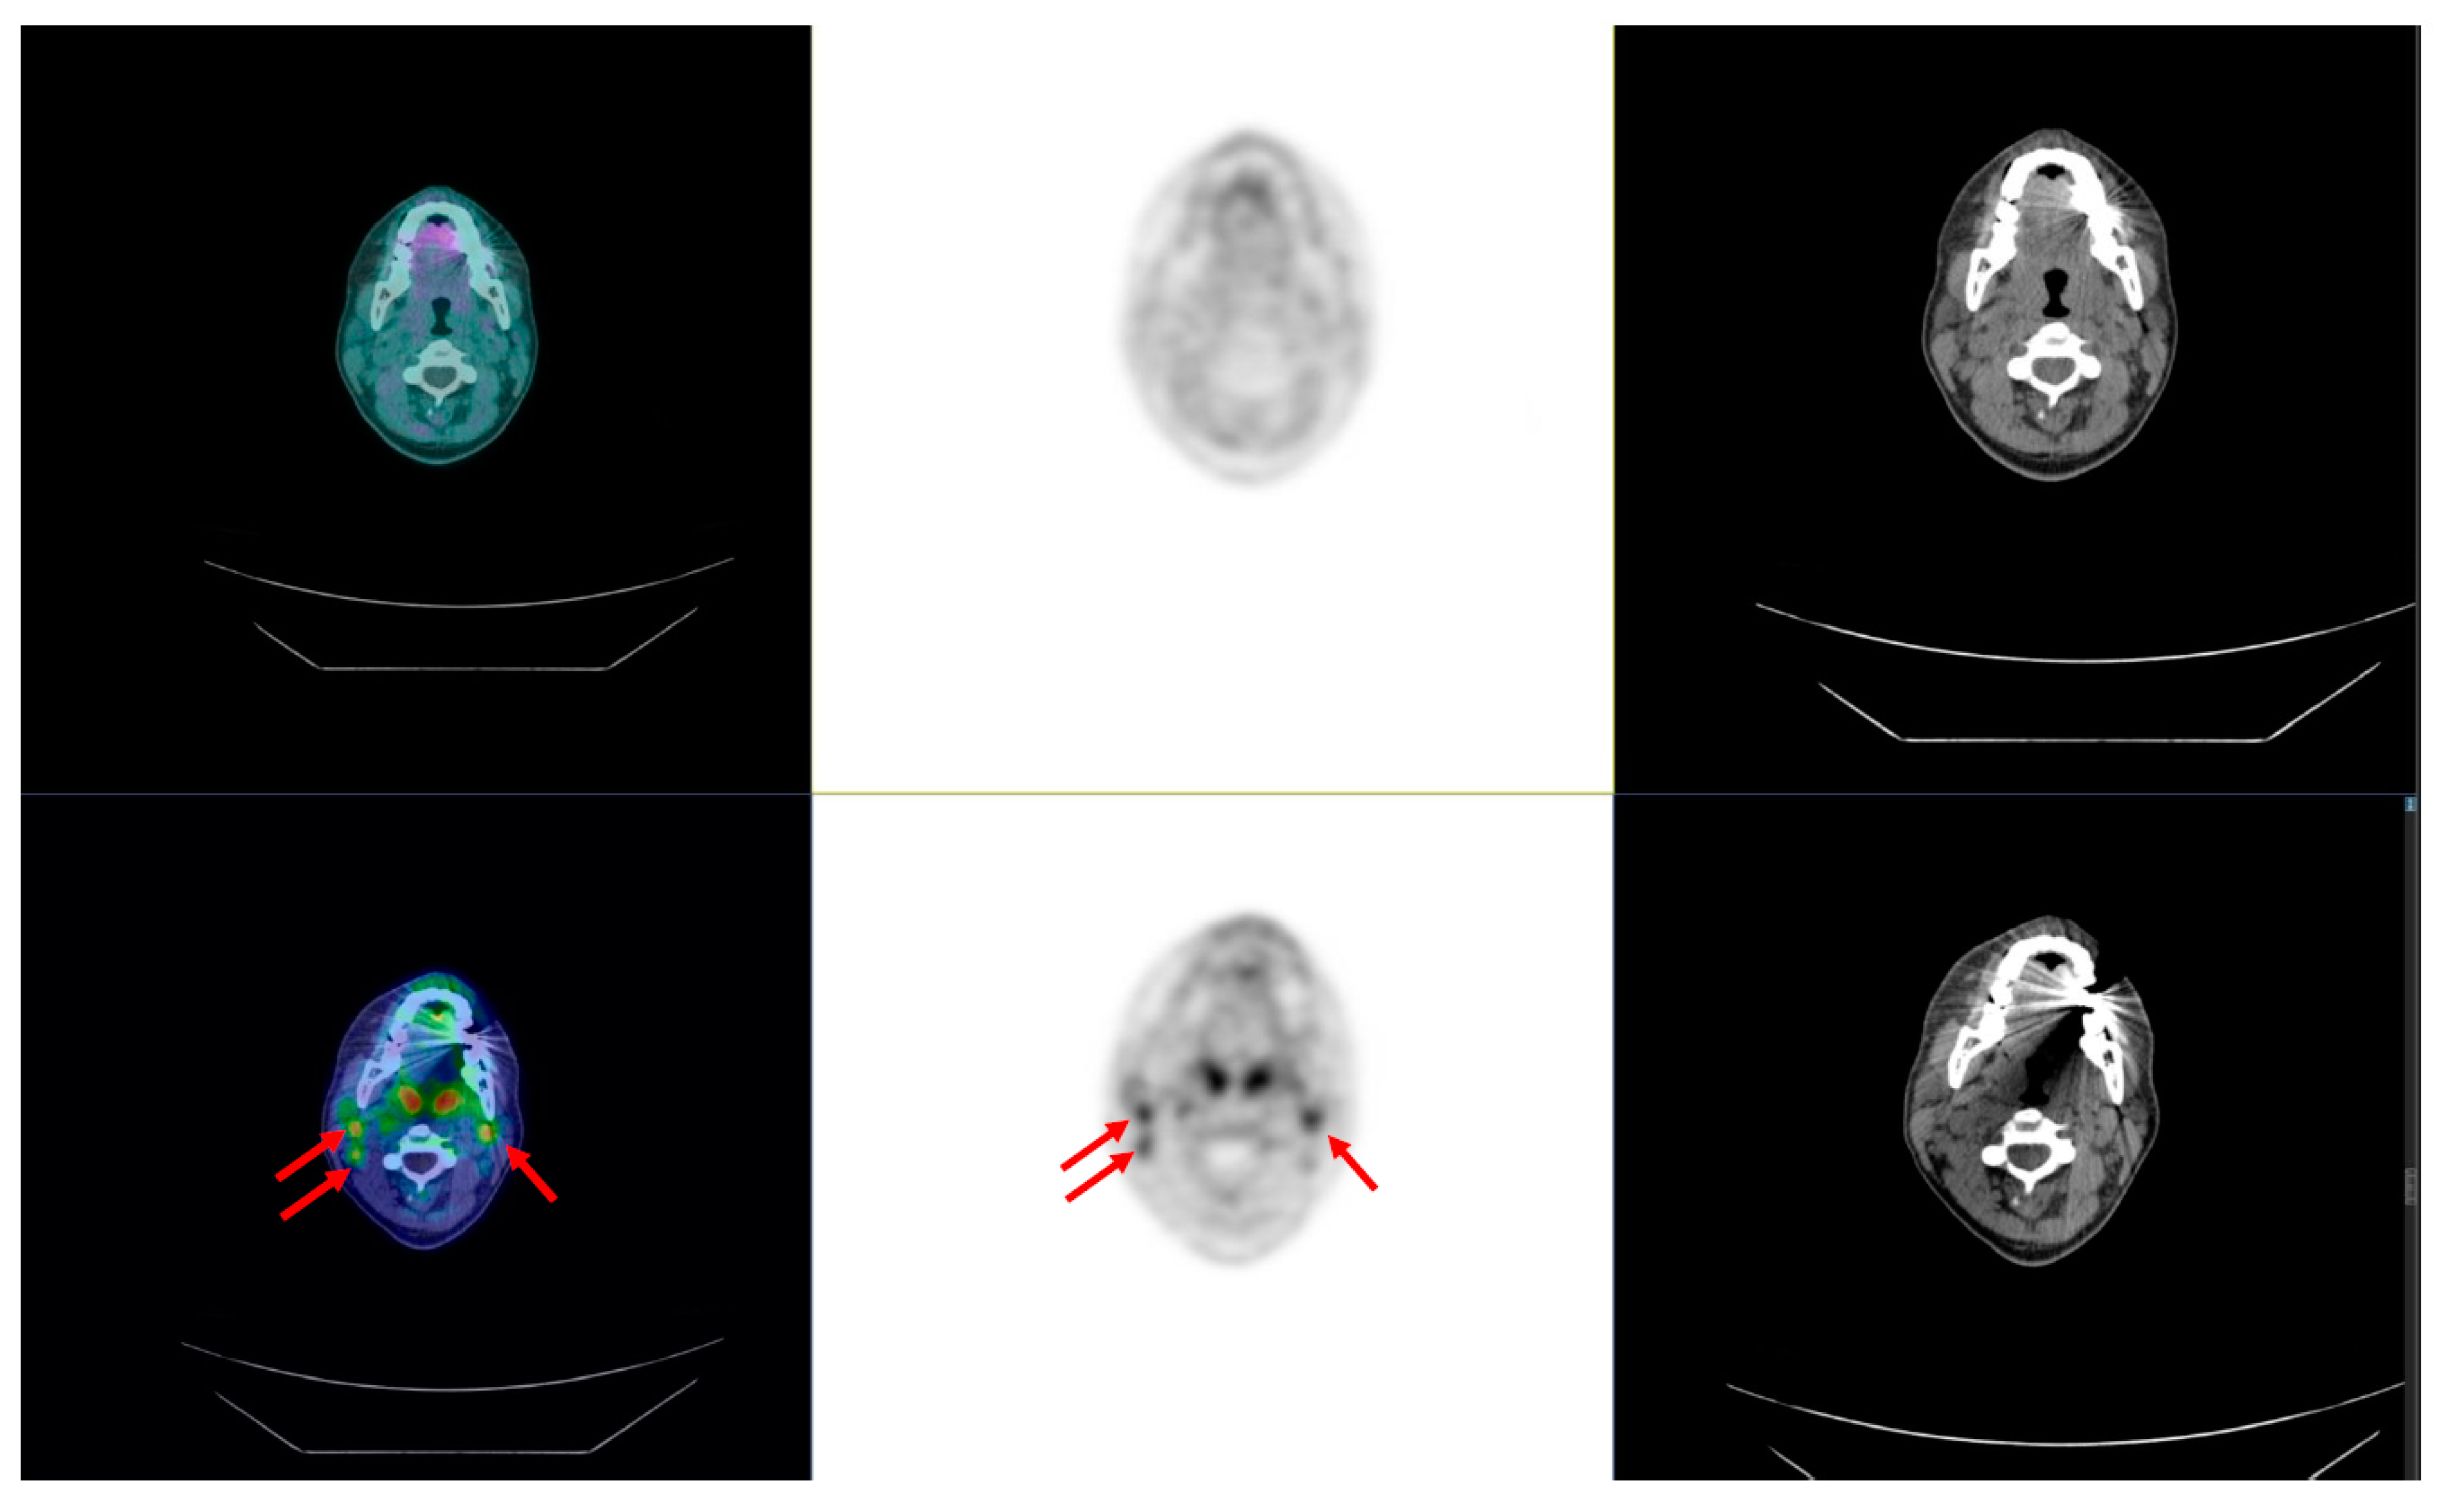

3.3.3. [18F]FDG Positron Emission Tomography/Computed Tomography (PET/CT)

3.4.2. Positron Emission Tomography